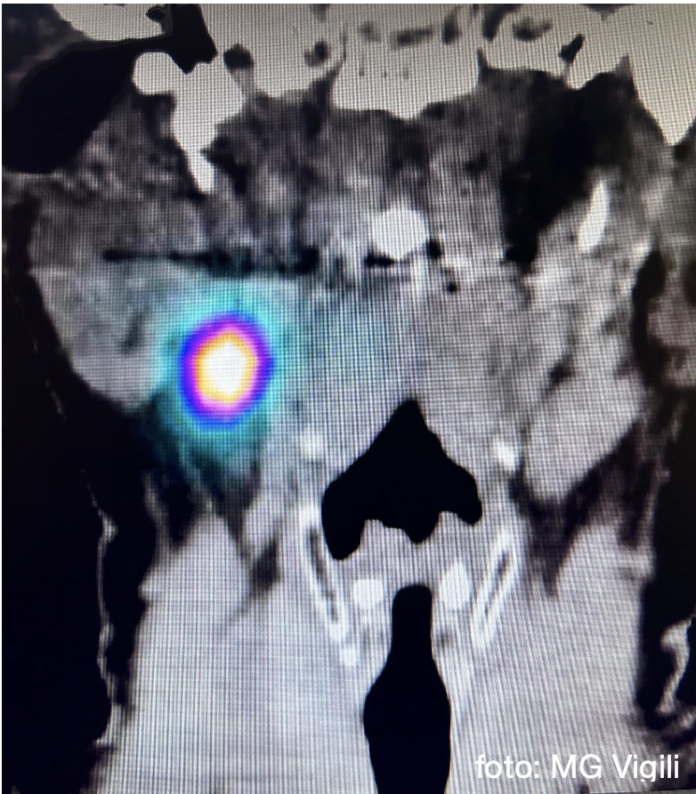

Valore del linfonodo sentinella nei tumori orali N0: l’esperienza giapponese. Uno studio giapponese, al fine di selezionare le indicazioni all’utilizzo della procedura del Linfonodo sentinella (SNB) nei tumori N0 del cavo orale, ha indagato il rapporto fra la profondità di invasione tumorale (DOI) e il diametro della lesione (LD), rispetto all’incidenza di metastasi evidenziate.

Sono stati presi in esame 3 trials condotti fra 2009 e 2016 in Giappone selezionando 158 pazienti.

Le percentuali di metastasi linfonodali riscontrate nella procedura di SNB sono risultate 21.3% nei T1 (LD= < 2 cm); 35.3% nei T2 (2-4cm) e 51.2% nei T3 (>4 cm).

Riguardo al DOI in alcuni casi T1(LD fra 8 e 20mm) con DOI fra 2 e 5 mm, la percentuale di metastasi è risultata pari al 40.9%.

Le significative percentuali di metastasi occulte riscontrate anche nei casi con LD < 20 mm e con DOI fino a 5 mm confermano che la procedura di ricerca del Linfonodo sentinella può essere estremamente efficace nello studio e trattamento dei tumori del cavo orale N0.